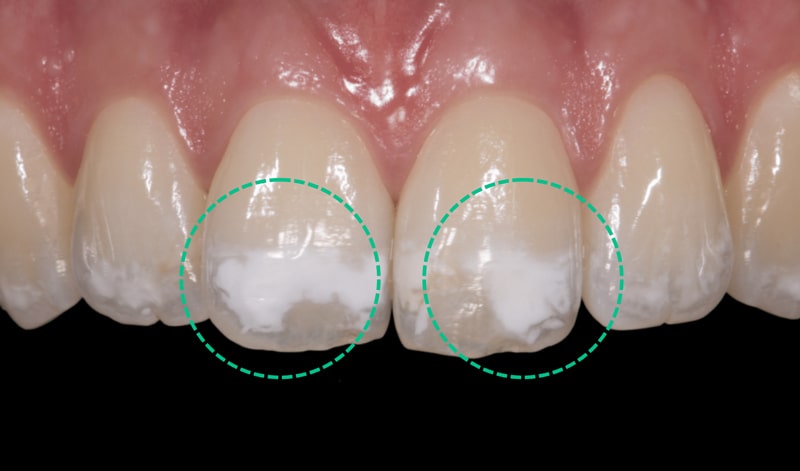

تغییر رنگ دندان به سفید (لکه های سفید روی دندان)

معمولا لکه های سفید روی دندان نشان دهنده دو حالت ذکر شده در زیر می باشد:

- فلوروزیس دندانی: مصرف بیش از حد فلوراید در دوران رشد دندان ها باعث ایجاد لکه های سفید روی دندان می شود.

- دمینرالیزاسیون:شروع فرایند پوسیدگی اولیه که در اثر اسید های تولید شده توسط باکتری های دهان رخ می دهد و باعث کاهش مواد معدنی دندان می گردد.